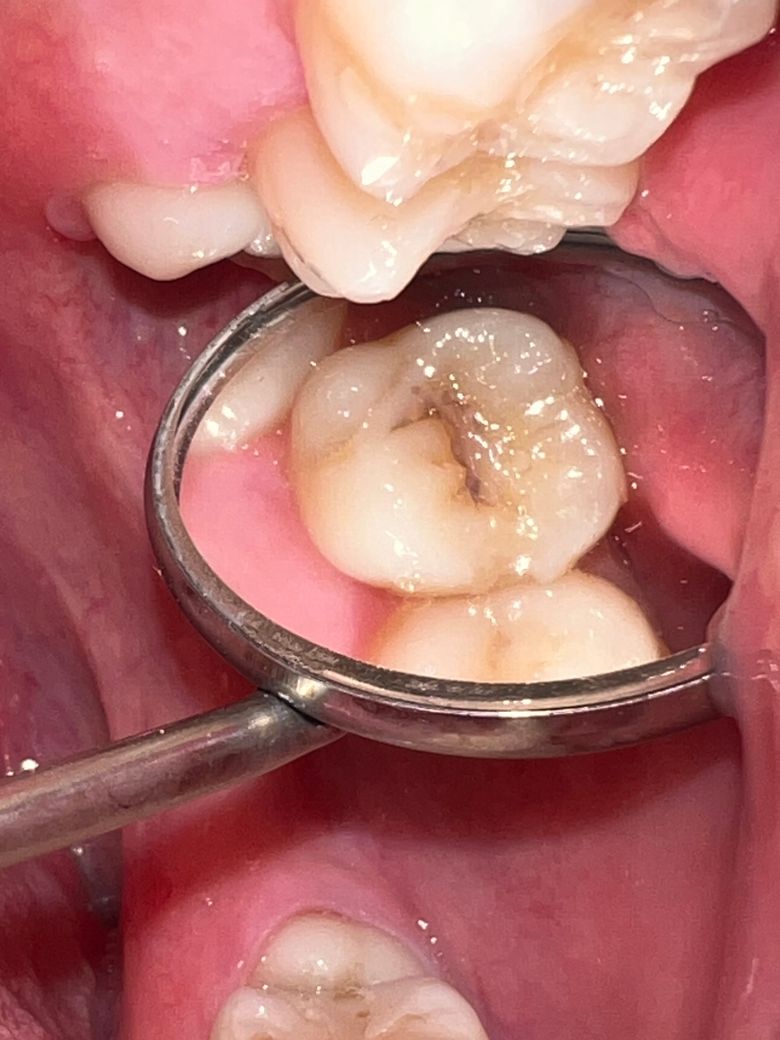

상악 어금니에 충치가 있는데 이정도면 인레이를 해야하는 수준인가요?

지금까지 충치가 약해서 치료를 레진치료밖에 안해봤습니다. 인레이하고 평생가는것도 아니고 8년정도 지나면 다시 교체해야하거나 악화되면 크라운할 수도 있으니까 레진을 하고싶긴하거든요. 인레이 어금니면 금을 추천많이 해주시는데 금니는 좀 미관상 이쁘진 않아서.. 그렇다고 세라믹은 어금니에 하기 불안하고… 인레이는 보통 치간 사이에 충치가 생겼을때 하는거라고 알고 있는데 저는 씹는 면만충치가 생겼습니다

통증은 하나도 없습니다. 어떤치료가 가장 적합할까요?

사진으로 보아 충치가 어느 정도 진행되었어며, 범위도 넓으니 인레이를 하는 것이 좋을 듯 합니다.

충치의 범위 자체가 큰 편이기 때문에 레진이나 인레이 치료 모두 가능해보입니다. 장단점이 있습니다.

사진상으로 봐도 충치가 넓어 보이고 깊어 보일것같습니다 엑스레이를 찍어보고 판단하겟지만 인레이를 해야될 가능성이 높습니다.

1. 엑스레이를 찍어봐야 충치가 얼마나 깊은지 알 수 있습니다.

2. 씹는면만 충치라면 일반적으로 레진으로 해도 됩니다.

3. 레진이 인레이보다 수명이 확실하게 길거나 하진 않습니다.